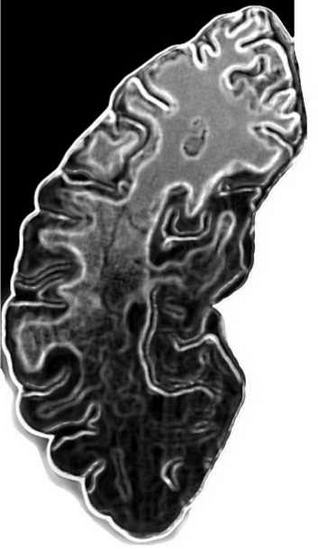

Сегодня отследить его динамику помогают точнейшие сканерные и измерительные технологии. Не только ЭЭГ, но и целый набор томографий и спектроскопии отражает электрическими или магнитными полями своеобразную «карту ГОЭЛРО» со вспышками мозговой активности. Нужна поистине фантастическая чуткость приборов: любое математическое вычисление или чтение текста включает множество процессов, длящихся миллисекунды. Это как передача эстафетной палочки по нейронным лабиринтам неокортекса вплоть до узла закрепления понятия и готовности к действию.

Присутствую на семинаре в СГА, где нейрологи, психофизиологи, педагоги, психологи задаются совершенно «крамольным» вопросом. По одной из современных теорий все богатство наших знаний закрепляется мыслеобразами в специфических узелках соединений между нейронными клетками — синапсах. Возникновение синапса видится так. Электрический импульс от нейрона к нейрону следует по отросткам между ними — аксонам и дендритам. В конце проводящего и принимающего «усика» скачок потенциала вызывает выброс химического нейромедиатора — образуется мостик, это и есть синапс. Работает уникальная и потрясающая сложнейшей отлаженностью природная электрохимическая машина. Каждый из 100 миллиардов нейронов, которыми одарила природа наш мозг, способен обрасти тысячами синапсов.

Скорость электроимпульса в нейронной сети — 400 километров в час. Представляете электропроводящие микроджунгли? Что такое по сравнению с ними любая государственная энергосистема! Мамино лицо времен далекого детства хранится в одном синапсе. Последствия от брошенной в стог сена спички — в другом. Знакомый пейзаж, плата за квартиру, правила движения, лечение насморка — весь ваш закрепленный опыт выдается из этого бесчисленного, но и строго фиксированного банка данных.